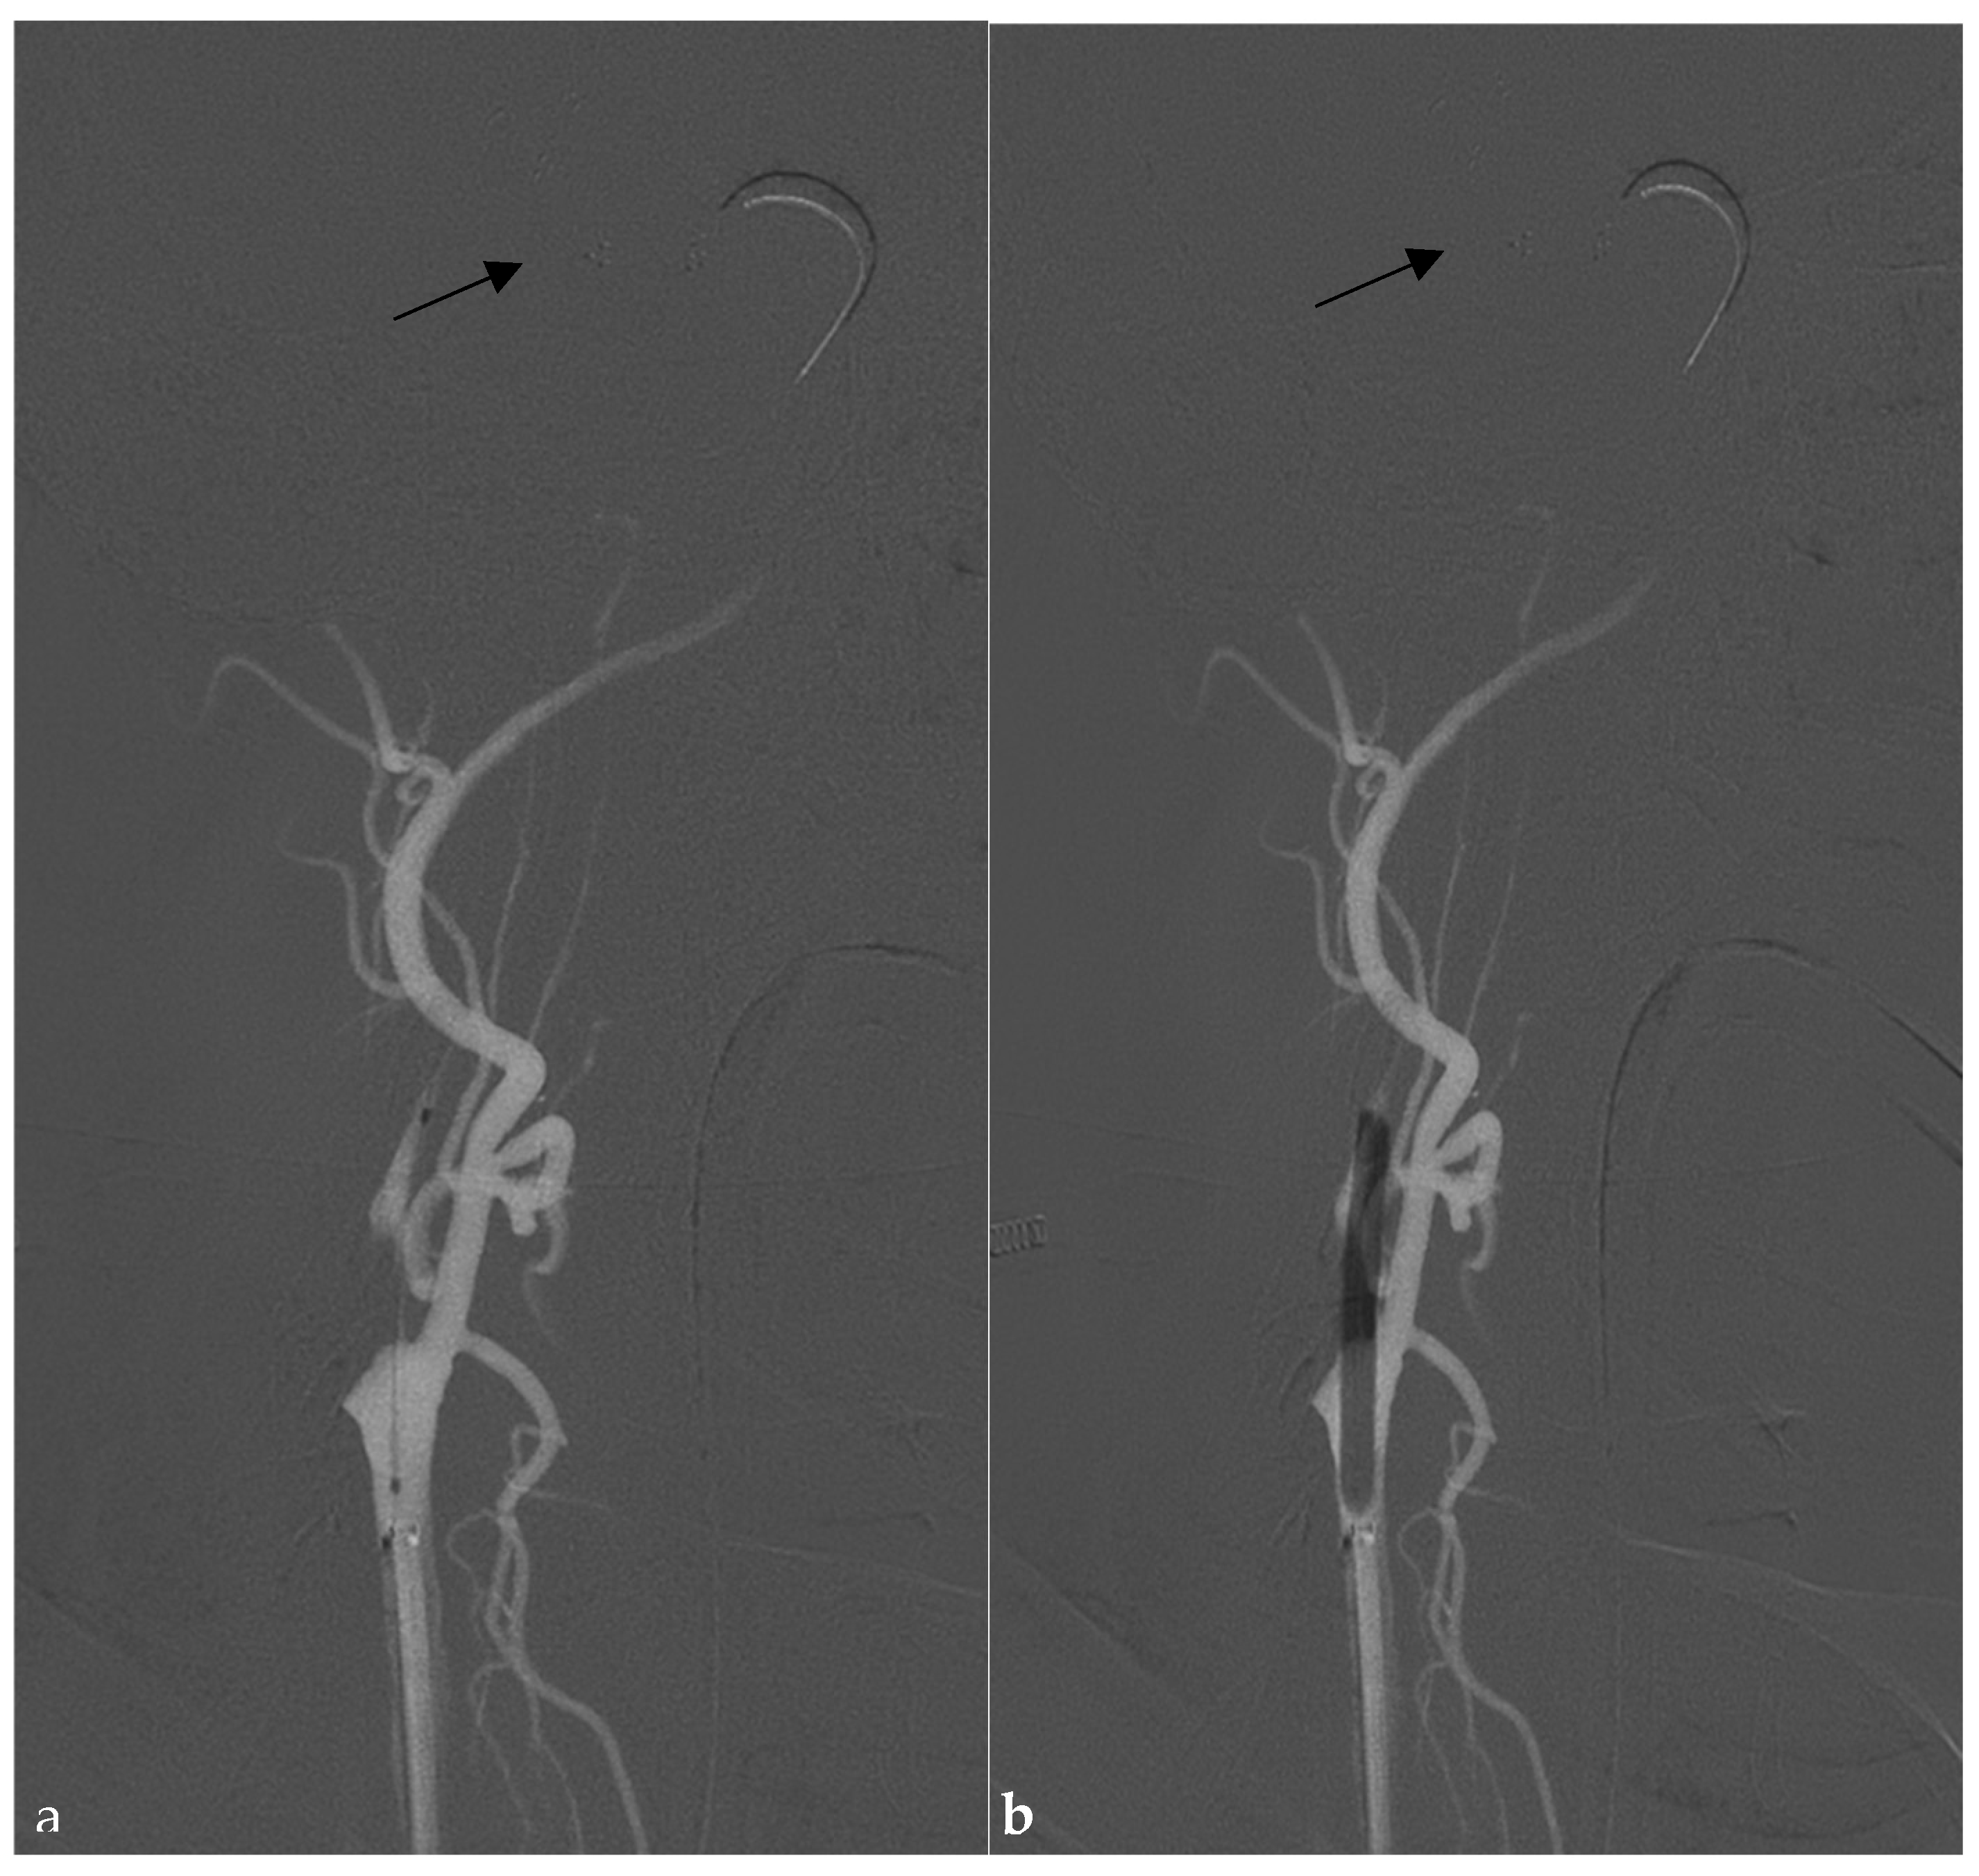

2.2. Endovascular Technique